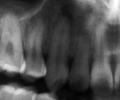

マルチブラケット終了時